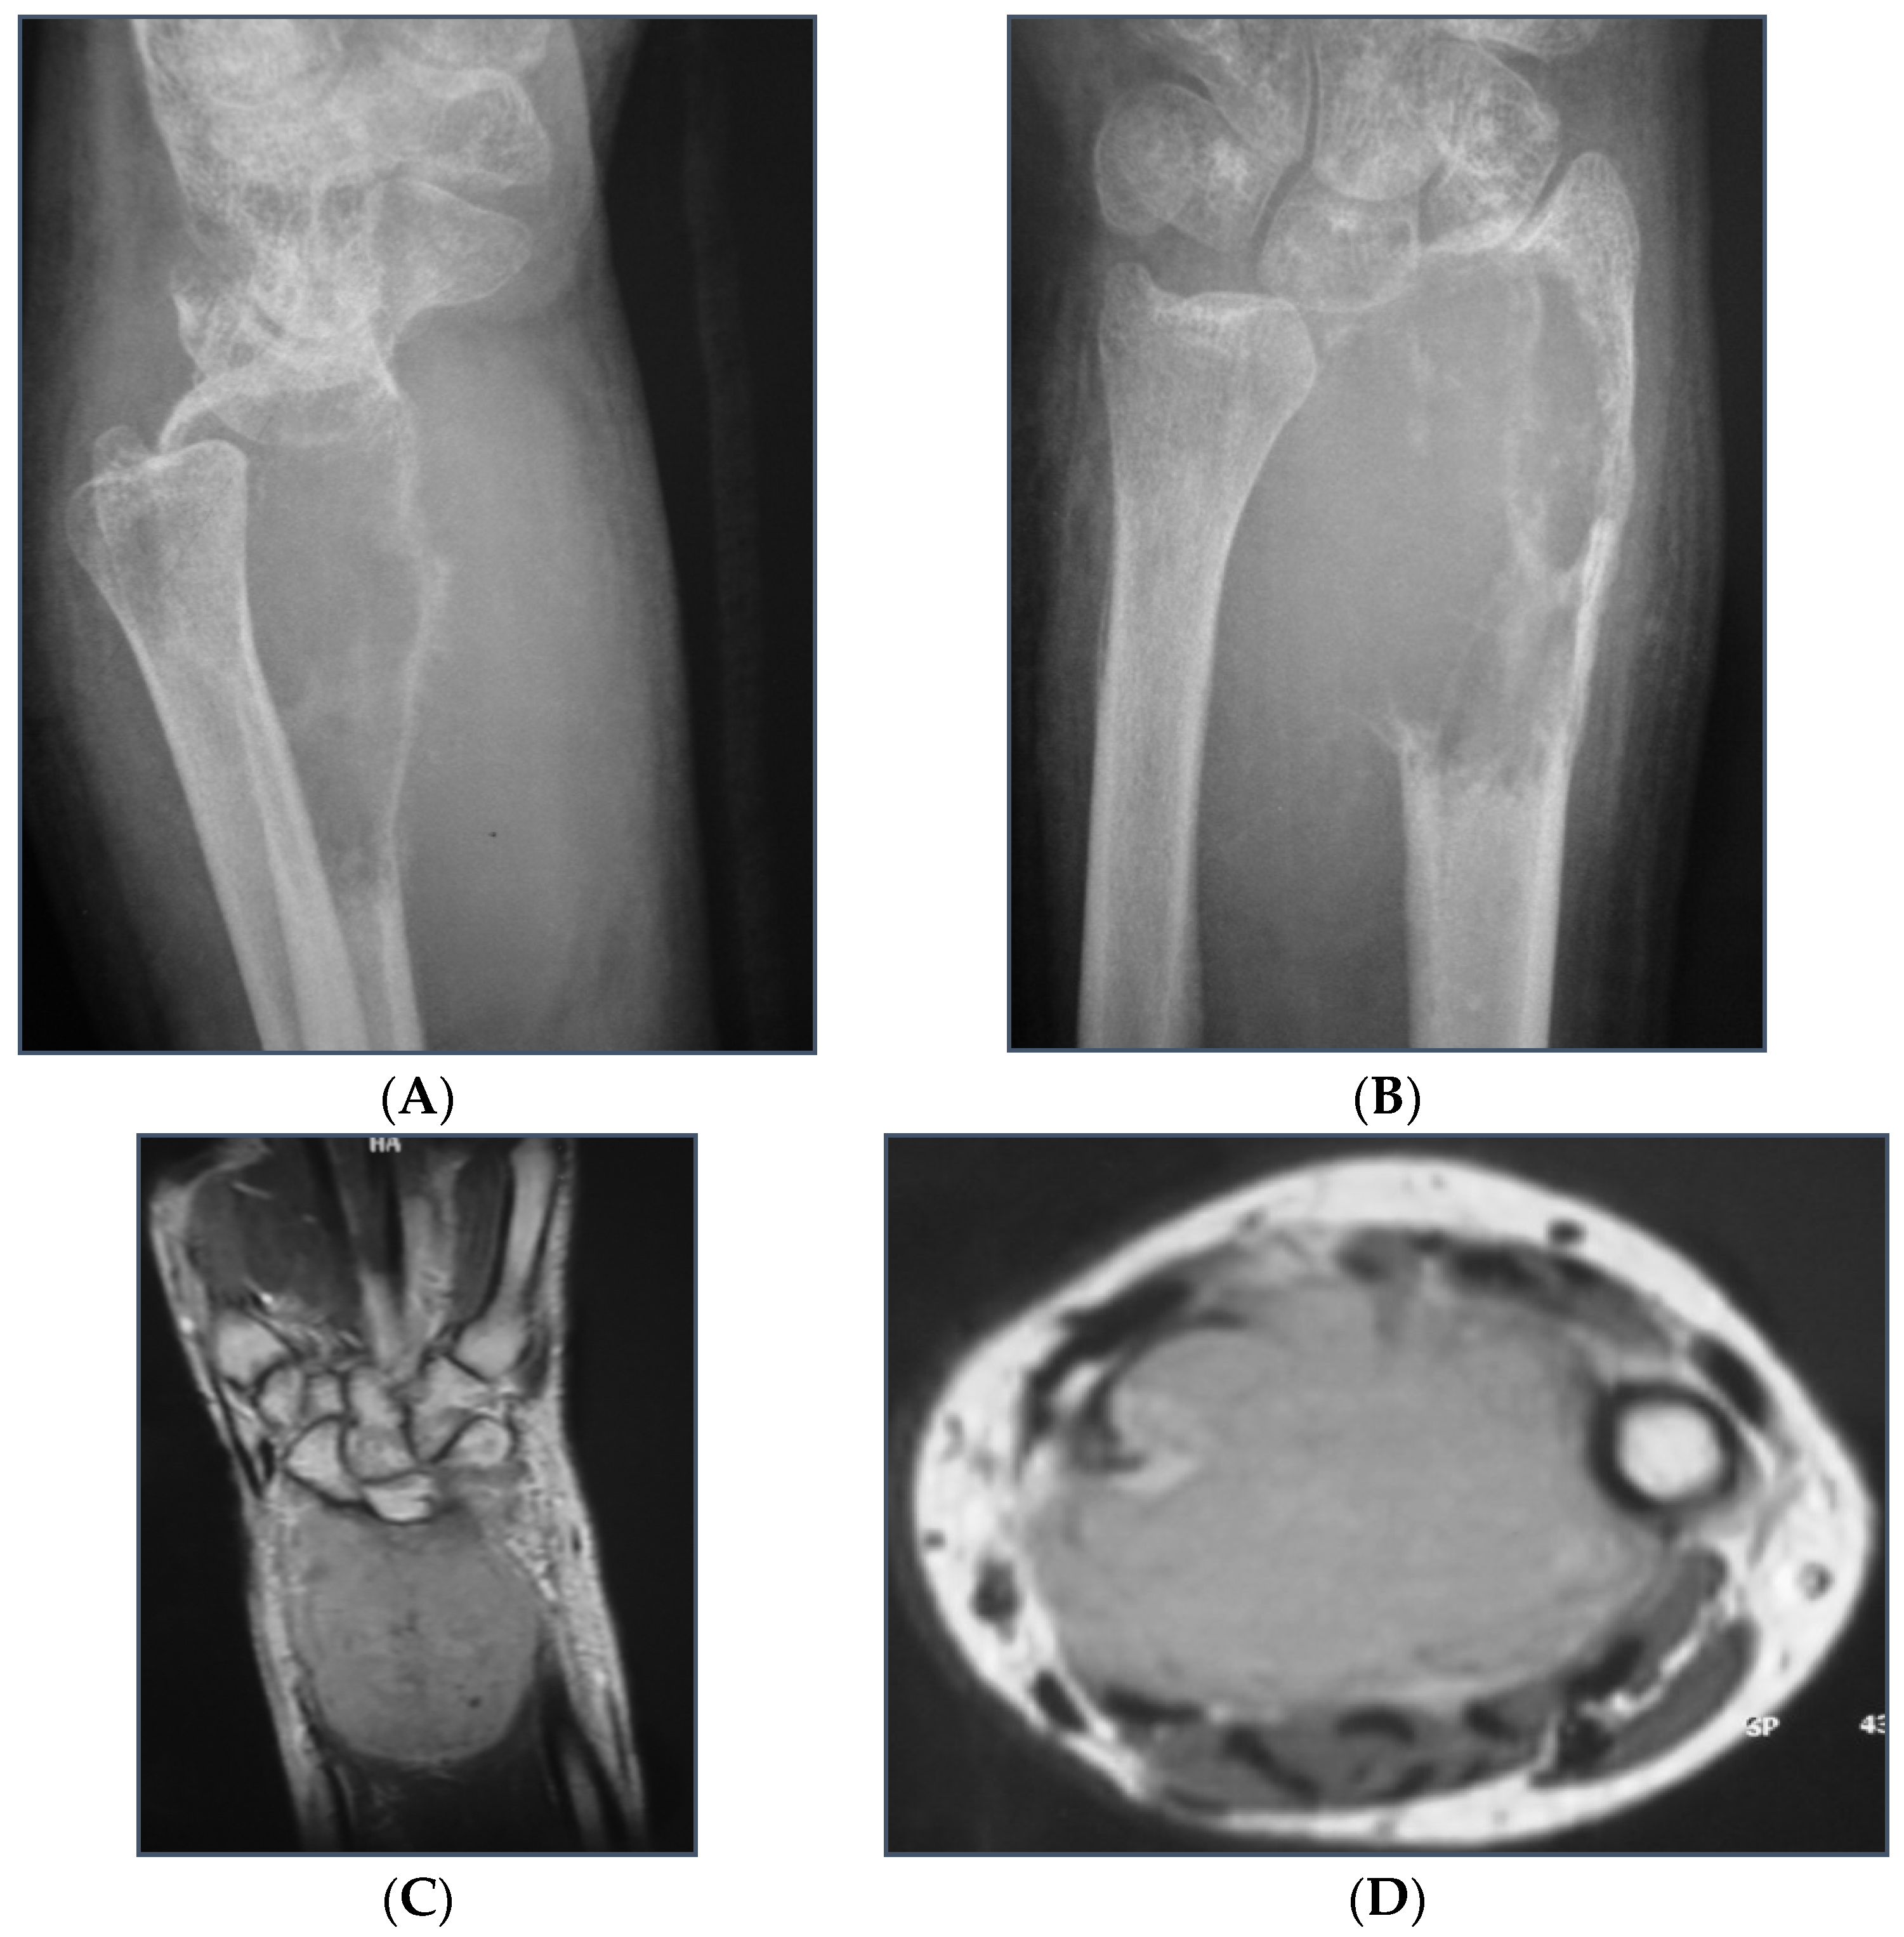

In cases of bone fracture non-union, the surgeon excised scar tissue along with the sequestrum until reaching bleeding bone, following the removal of previously inserted metalwork. For tumor excision cases, the surgeon resected the bone tumor with clear margins or the entire compartment in cases of tumor-induced bone cortex breakage (Figure 1). At this stage, the length of the bone defect was measured to determine the appropriate length of the fibular graft to be harvested (Figure 2). The fibular graft fixation was accomplished using dynamic compression plates (DCPs) or anatomical plates, with a minimum of six cortices engaged on each side using either simple or locking screws (Figure 3). Once the osteosynthesis is completed, it is time to proceed with the vessel anastomosis. First, the peroneal vein is anastomosed to the radial or ulnar vein using 8-0 nylon monofilament sutures. Following this, the surgeon performs the arterial anastomosis using the same type of suture as previously. Simple interrupted stitches are preferred over a continuous suture technique and the anastomosis could be either end to end or end to side using a microscope.

Figure 2. (A,B): Measuring the skeletal defect is essential to harvest the appropriate length of the fibular graft.